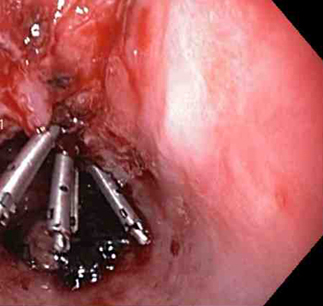

A mechanical method (e.g., clips) with or without adrenaline (epinephrine). In practice, both through-the-scope clips (TTSC) and over-the-scope clips are options depending on availability and expertise. However, for MWT, TTSC usually suffice.[Figure caption and citation for the preceding image starts]: Mallory Weiss tear after application of through-the-scope clip results in haemostasisFrom the personal collection of Douglas Adler; used with permission [Citation ends].

Through-the-scope clips (TTSC), alone or in combination with adrenaline injection to clear the visual field

TTSC are widely available, have a robust evidence base and are usually sufficient to control bleeding in MWT.

TTSC use is as safe and effective as other methods for controlling actively bleeding lesions.[76][77][78][Figure caption and citation for the preceding image starts]: Mallory Weiss tear after application of through-the-scope clip results in haemostasisFrom the personal collection of Douglas Adler; used with permission [Citation ends].

[Figure caption and citation for the preceding image starts]: Mallory Weiss tear after application of through-the-scope clip results in haemostasisFrom the personal collection of Douglas Adler; used with permission [Citation ends].